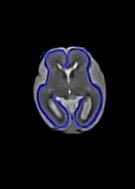

Fetal cortical plate segmentation is essential in quantitative analysis of fetal brain maturation and cortical folding. Manual segmentation of the cortical plate, or manual refinement of automatic segmentations is tedious and time-consuming. Automatic segmentation of the cortical plate, on the other hand, is challenged by the relatively low resolution of the reconstructed fetal brain MRI scans compared to the thin structure of the cortical plate, partial voluming, and the wide range of variations in the morphology of the cortical plate as the brain matures during gestation. To reduce the burden of manual refinement of segmentations, we have developed a new and powerful deep learning segmentation method. Our method exploits new deep attentive modules with mixed kernel convolutions within a fully convolutional neural network architecture that utilizes deep supervision and residual connections. We evaluated our method quantitatively based on several performance measures and expert evaluations. Results show that our method outperforms several state-of-the-art deep models for segmentation, as well as a state-of-the-art multi-atlas segmentation technique. We achieved average Dice similarity coefficient of 0.87, average Hausdorff distance of 0.96 mm, and average symmetric surface difference of 0.28 mm on reconstructed fetal brain MRI scans of fetuses scanned in the gestational age range of 16 to 39 weeks. With a computation time of less than 1 minute per fetal brain, our method can facilitate and accelerate large-scale studies on normal and altered fetal brain cortical maturation and folding.